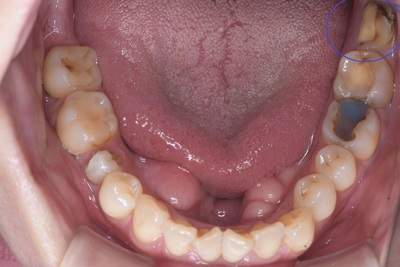

親知らずの抜歯症例

- 抜歯前の口腔内写真(下)

- 抜歯前の口腔内写真(上)

- 抜歯前写真(レントゲン)

- 抜去歯(左下)

- 抜去歯(左上)

- 抜去歯(右上)

| 年齢 | 50代・女性 |

|---|---|

| 主訴 | 右上と左上下の親知らず |

| 親知らずの生え方 | 真っ直ぐに生えている |

| 抜歯時間 | 説明、麻酔含め各約30分 |

| 費用 | 各約1,240円(保険診療3割負担) (2024年12月現在) |

| 抜歯内容 | 抜歯後の負担を考慮して、右上、左上、左下の順で日にちを分けて抜歯しました。 |

| 治療方針 | 親知らずの手前の7番の虫歯治療が必要なため、先に虫歯になっている親知らずの抜歯から始めました。 |

| 担当者所見 | 左上親知らずは、メタルの被せ物が抜歯の際に外れ、中は虫歯で歯が溶けていました。 右上、左下もレジンのような材料で治療した痕がありましたが、いずれも大きく欠けており、歯として機能していませんでした。 |